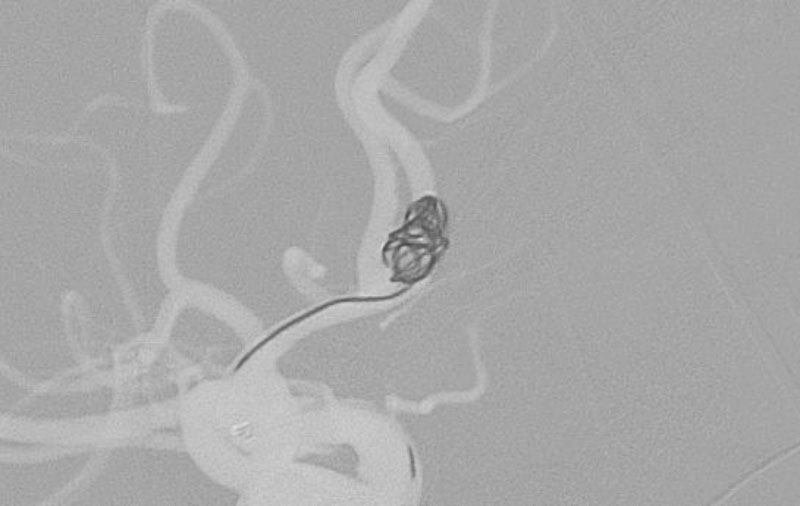

No.1596 手術中